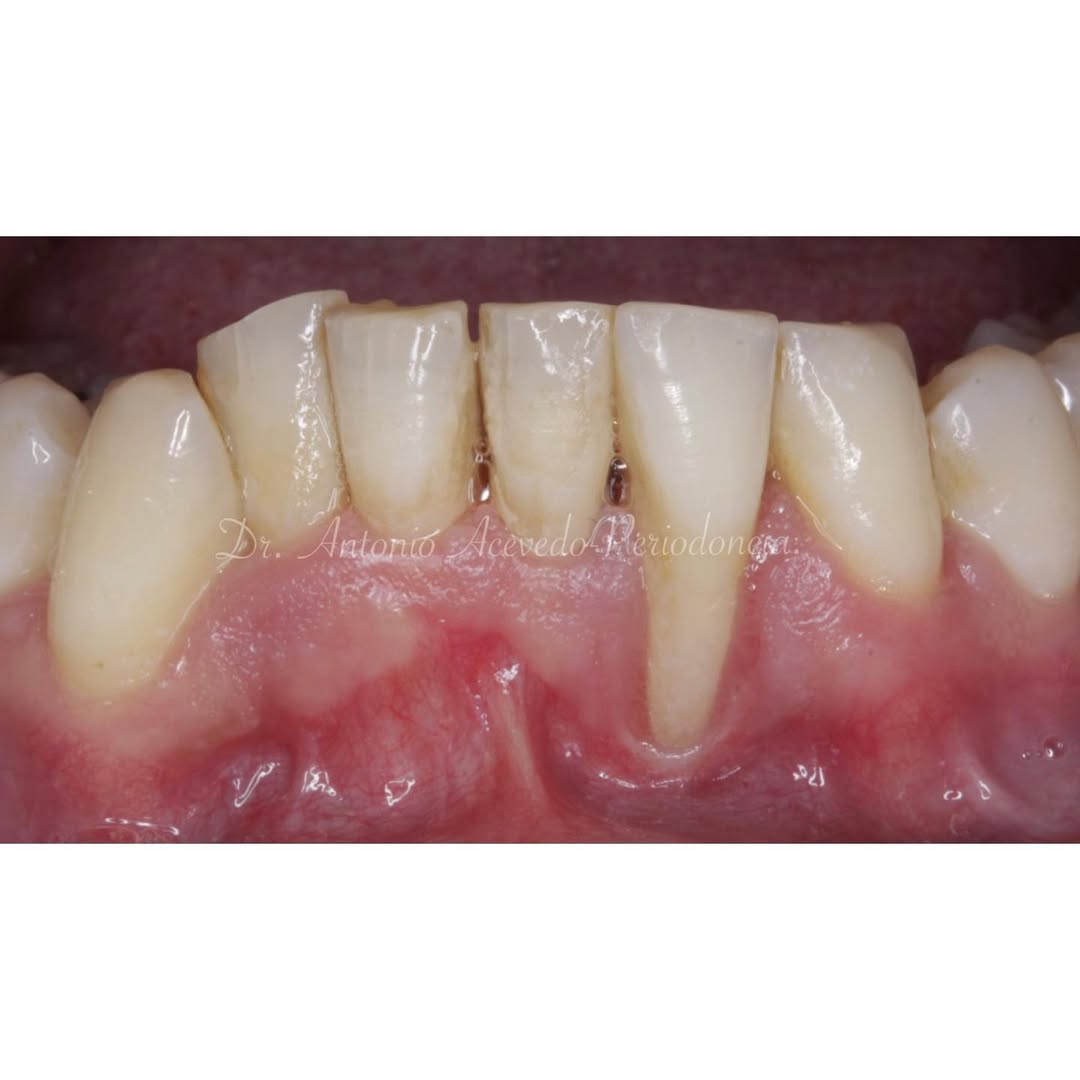

Durante una mañana, asistirás a una Cirugía Mucogingival de recubrimiento radicular de recesiones múltiples en IV y V sextante (36 a 43).

Aprende la planificación y técnica de la cirugía Mucogingival para el recubrimiento de recesiones y aumento de banda queratinizada en el sector anteroinferior

Durante una mañana, asistirás a una Cirugía Mucogingival de recubrimiento radicular de una recesión unitaria en 31 con frenillo asociado. Gracias al uso del microscopio y a la proyección en tiempo real en pantalla, verás exactamente lo mismo que veo yo durante la cirugía, sin tener que estar